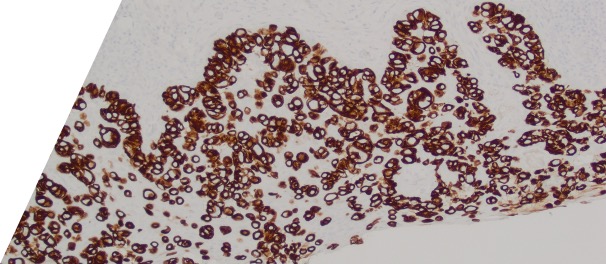

Large round malignant cells with pale cytoplasm and enlarged nucleolus and prominent nucleoli are present within the epidermis. The cytoplasm contains mucin. Differential diagnosis include HSIL, Paget disease (primary or secondary), and melanoma in situ. The lesional cells are strongly positive for CK7, CK20, CAM5.2 and GATA3, scattered positive for p63; and patchy staining for p16, negative for ER and SOX10. High-risk HPV-ISH is negative.

Patient's history of invasive high-grade urothelial carcinoma is shown. The tumor cells showed similar morphological features to the tumor cells in current specimen. The findings are compatible with secondary involvement by previously diagnosed urothelial carcinoma.